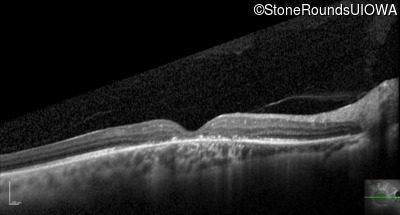

Optical Coherence Tomography - Right - 20/60 sc

Exemplar / OCT Stack

Optical Coherence Tomography - Left - 20/100 sc